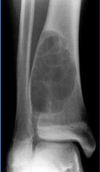

**COULD SHOW ON BOARD!** What is this a picture of?

Osteosarcoma arising in Paget disease! 1% of patients with Paget disease will develop osteosarcoma You can tell this is arising in Paget because of the mosaic lines (changing direction) in the bone